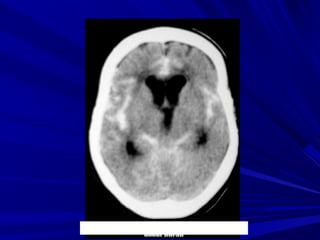

Phát hiện xuất huyếtPhát hiện xuất huyết

Xuất huyết là các vùng tăng đậm độ và có thể thấyXuất huyết là các vùng tăng đậm độ và có thể thấy

trong các bệnh lý:trong các bệnh lý:

Tụ máu ngoài màng cứng,Tụ máu ngoài màng cứng,

Tụ máu dưới màng cứngTụ máu dưới màng cứng

Xuất huyết màng nãoXuất huyết màng não

Xuất huyết não thấtXuất huyết não thất

Xuất huyết trong nãoXuất huyết trong não

Phân biệt hoá vôi và xuất huyết nhỏ vùng nhân nềnPhân biệt hoá vôi và xuất huyết nhỏ vùng nhân nền

Phân biệt xuất huyết cầu não với hình ảnh nhiễuPhân biệt xuất huyết cầu não với hình ảnh nhiễu